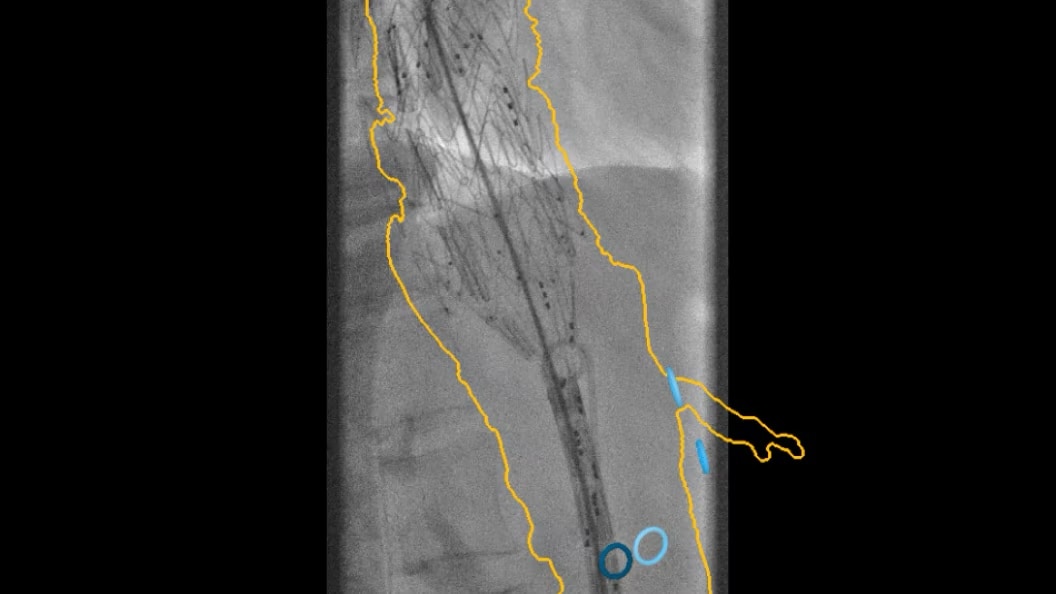

Advanced CBCT for accurate diagnostic and treatment planning

Experience the precision of cone-beam CT, offering high-resolution 3D imaging for accurate diagnostics and treatment planning with enhanced safety and efficiency.